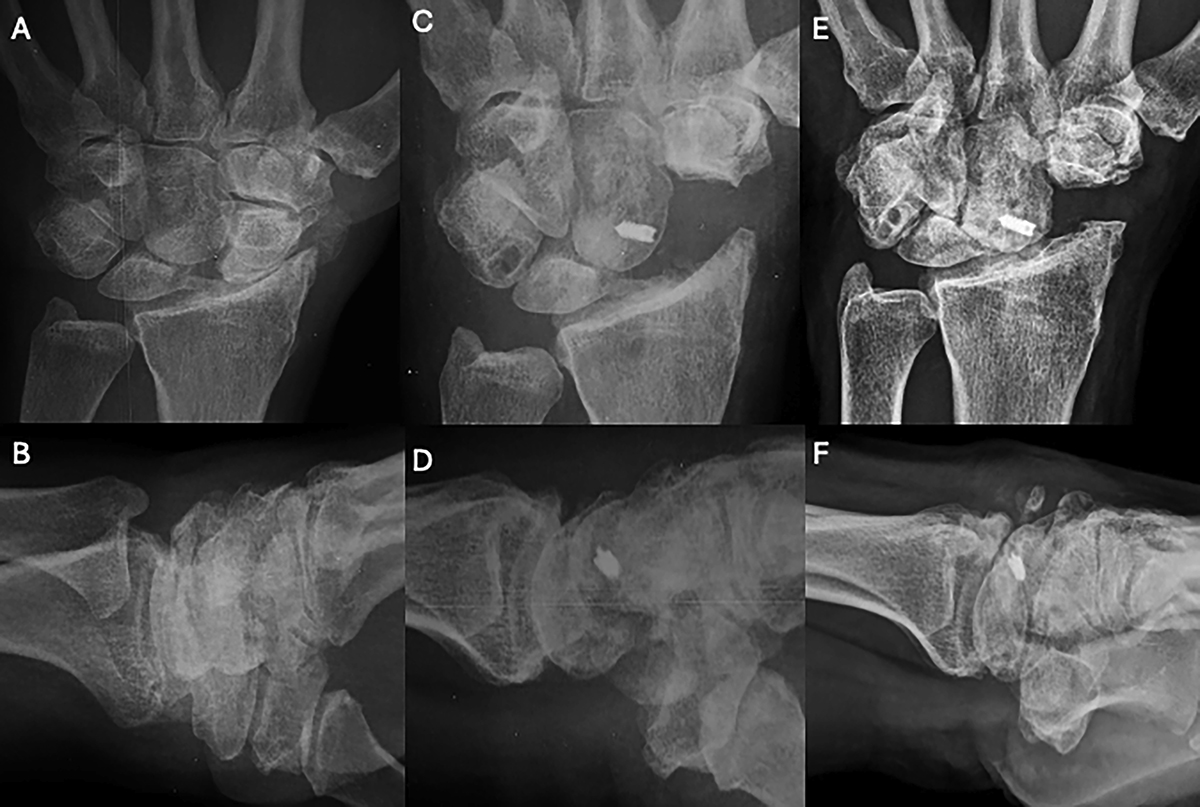

Clinical case of FCR Tenodesis transosseous T (Osseous grip) and Scaphoid excision. A and B. Preoperative wrist X-rays of SLAC stage II (AP and Lateral views). C and D. Postoperative wrist X-rays (AP and Lateral views) after 2 months. E and F. Postoperative wrist X-rays (AP and Lateral views) after 8.5 years. Source: Dr. Emmanouil Apergis.